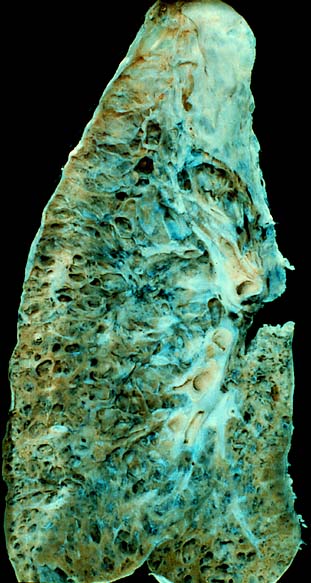

Fibrosis pulmonar es una enfermedad respiratoria crónica y progresiva caracterizada por la formación de excesivo tejido conectivo (fibrosis), engrosando las paredes de los tejidos pulmonares. Sobre la base de estas tasas, la prevalencia de la fibrosis pulmonar en los Estados Unidos podrían variar de más de 29 000 a casi 132 000, con base en la población de 18 años o más en el año 2000. Por ello es muy importante que en el marco de del Día Mundial de la Fibrosis Pulmonar Idiopática, las autoridades de salud, la comunidad médica y público en general se unan en el trabajo imprescindible de dar visibilidad, sensibilizar y sobre todo abogar por el acceso a tratamientos que ayuden a los pacientes a respirar mejor y mejorar su calidad de vida.

La fibrosis pulmonar idiopática es una enfermedad progresiva en la que se van produciendo cicatrices en ambos pulmones que dificultan el intercambio de oxígeno y provocan tos crónica y disnea o falta de aire.

La sustitución cicatricial del tejido normal de pulmón provoca disminución irreversible de la capacidad de difusión de oxígeno (oxigenación).[3] Por otra parte, la disminución de la distensibilidad pulmonar por fibrosis conforma una enfermedad pulmonar restrictiva. La genética puede desempeñar un papel en la causa de la fibrosis pulmonar.[19] Si más de un miembro de una familia tiene fibrosis pulmonar, la enfermedad se llama fibrosis pulmonar familiar.[19] La fibrosis pulmonar puede no tener causa conocida, en cuyo caso se denomina fibrosis pulmonar idiopática, o puede ser causada por un gran número de variables, en cuyo caso suele remitir al eliminar el factor desencadenante.

La fibrosis pulmonar es una enfermedad pulmonar intersticial caracterizada por la sustitución de tejido pulmonar por tejido colágeno.